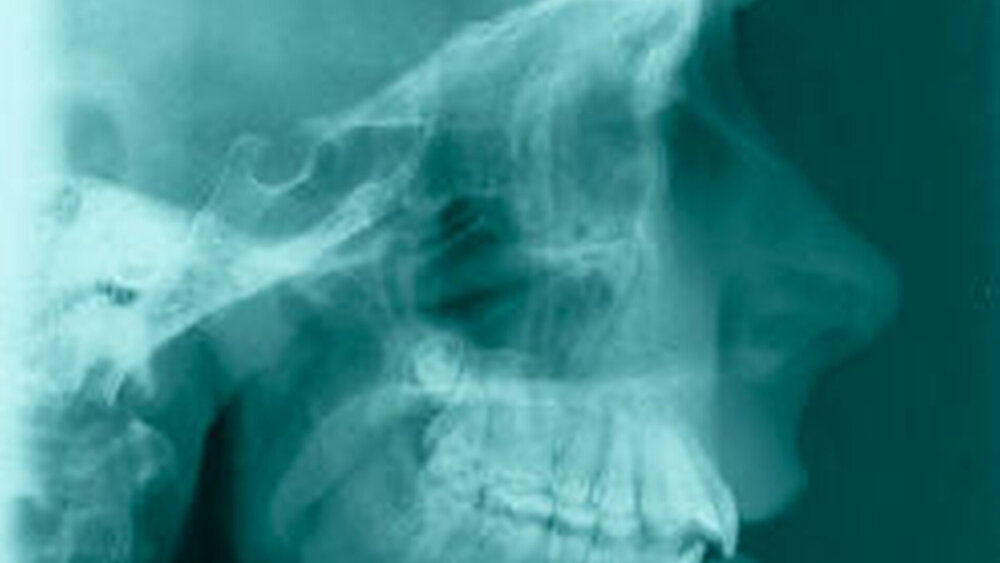

Bereits 2004 wies Carla Evans [Evans, 2005] auf das Risikomanagement bei Allgemeinerkrankungen hin und stellte am Beispiel der JIA dar, dass Unterkieferrücklagen und frontal offene Bisse aus der Kiefergelenkzerstörung entstehen können. Die Röntgenaufnahmen einer JIA-Patientin mit oligoartikulärer Form und Beteiligung des rechten Kiefergelenkes zeigen den typischen Verlauf sehr gut. Bei ursprünglich sehr dezenten Befunden, wie einer s-förmigen Mundöffnung von 44 mm, einer geringen Mittenabweichung um 2 mm nach rechts und einem frontal offenem Biss klagte sie über Schmerzen beim Essen, was den Anlass zur weiteren Diagnostik bot. Die erste Panoramaröntgenschichtaufnahme (Abbildung 1a-c) zeigt auf der rechten Seite einen abgeflachten Kondylus und eine bereits verstrichene Fossa condylaris. Ein Jahr später vermittelt das Fernröntgenseitenbild (Abbildung 1d) trotz fortschreitender kondylärer Resorption ein harmonisches Bild, während nach drei Jahren bei voranschreitendem Abbau des rechten Kondylus (Abbildung 1e) eine Rücklage der Mandibula und eine Bissöffnung manifest sind (Abbildung 1f).

Die Fernröntgenseitenaufnahme in Abbildung 2a zeigt ein „rheumatisches“ Profil mit retraler, hypoplastischer Mandibula, oft kombiniert mit einer Schwäche des M. masseter auf der betroffenen Seite. Der Funktionsschmerz erzeugt „Kaufaulheit“. Die Gesichtsasymmetrie (Abbildung 2b) betrifft meist Kinn, aufsteigenden Ast und die Höhe der Kieferwinkel. Auch die nicht dentoalveoläre Mittellinienverschiebung kann auf eine JIA hinweisen. Kreuzbisse variieren in Abhängigkeit vom Grad der Unterkiefermittenabweichung. Gemeinsame Auftreten eines frontal offenen Bisses und eines vergrößerten Overjet sind als klinische Anzeichen zu bewerten.